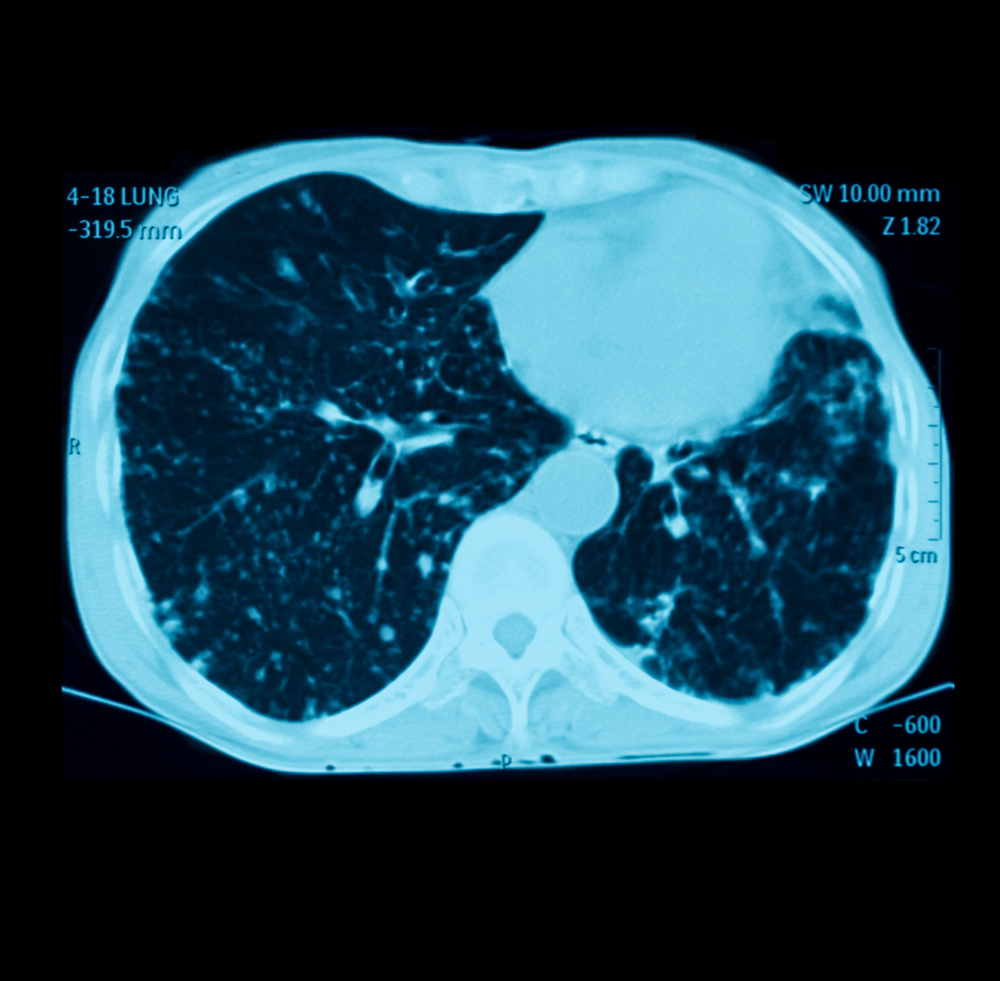

呼吸器領域の画像解剖と症例 兵庫医科大学放射線科 小林薫 第4回兵庫県放射線技師会読影セミナー 平成28年12月17日 本日の内容 •胸部単純x線写真について –基本的事項 •胸部ct:読影に必要な解剖について –肺野区域解剖 •各種症例の画像と読影のポイント –肺炎 –胸膜/胸壁疾患 –その陰嚢水腫、Nuck水腫 臍腸管遺残・尿膜管遺残 胚細胞性腫瘍 肺分画症 肥厚性幽門狭窄症 ヒルシュスプルング病 副耳 腹壁破裂 便秘 肺分画症の画像所見 肺底部に多房性嚢胞〜充実腫瘤 として認められる。 大動脈から分岐する異常血管を見つける ことが診断に有用。 ご案内 腹部画像診断を学べる無料コンテンツ 4日に1日朝6時に症例が配信され、画像を実際にスクロールして読影していただく講座です。現状無料公開

縦隔腫瘍、CCAM、肺分画症 著者 Author(s) 藤岡, 一路 / 芳本, 誠司 掲載誌・巻号・ページ Citation 周産期の画像診断 第二版,周産期医学 / 周産期医学編集 委員会編, Vol 43, 13 増刊号4486 刊行日 Issue date 1312 資源タイプ Resource Type Journal Article / 学術雑誌論文 版区分 Resource Version publisher 権利 Rights DOI肺分画症 硬化性血管腫 肺動静脈瘻・奇形 特発性肺線維症(ipf) 60歳過ぎた男性 60%以上 ほとんどの治療法は無効 死亡率は5年で50~70% 呼吸細気管支炎関連間質性肺疾患(rbild) 40~50歳 (やや男性に多い) 90%以上 禁煙、ステロイド 死亡はまれ 上に戻る 胸部レントゲン写真の所見別VR 画像を作成することで、さらに血管走行の詳細がはっきりする。 >診断 : 肺分画症( intralobar pulmonary sequestration ) >解説 : 分画肺は大動脈から分岐する異常動脈から血流を受け、以下の 2 型に分類される。原則として正常気管支とは交通がない。

肺葉内肺分画症の画像診断への寄与 松島 秀和 1)高柳 昇 生方 幹夫 徳永 大道 佐藤 長人 1)倉島 一喜 柳沢 勉 杉田 裕1) 星永進2) 河端 美則3) 金沢 実1) 要旨:自験の肺葉内肺分画症12例において,胸部ct所見を検討した.分画肺を気管支構造の性状と肺野(congenital cystic adenomatoid malformation;CCAM),肺分画症などの先 天性疾患を背景にした治療抵抗性の感染症もあり,注意すべき疾患である。 また,肺炎から肺膿瘍や膿胸への進展,肺出血,肺梗塞,血管炎の合併の有無も考慮 する。ある程度これらの可能性が除外できたと判断されたら非 肺分画症とは、正常な空気の通り道(気管支)と交通がなく、肺動脈ではなく大動脈からの血液で栄養される異常な構造の肺のことを指します。肺は空気中の酸素を身体に取り込み、体外に二酸化炭素を排出する役割を持つ臓器です。そのため、肺が正常にはた療・介護関連肺

症例0 肺葉内肺分画症 Ct 症例 肺 X線写真

症例084 肺葉外肺分画症 Ct 症例 X線写真 アトラス